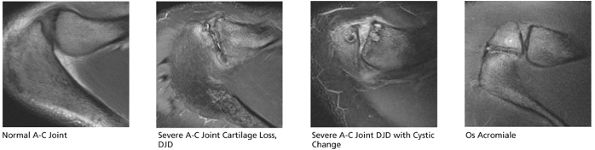

FIGURE 8.29 ● (A) Coronal T1- or PD-weighted images are used to evaluate the distal acromion. (B) Coronal FS PD-weighted images show the majority of the cranial-to-caudal extent of the subscapularis tendon. This image is used to triangulate on subscapularis tears suspected on other planes. Most commonly, tears of the subscapularis begin in the superior articular margin of the tendon. (C) In the setting of supraspinatus tears, coronal T1- or PD-weighted images at or near this image slice are best for assessment of supraspinatus atrophy. (D) Coronal FS PD-weighted images display two important anatomic structures. The first is the anterior-most portion of the distal supraspinatus tendon (also called the “anterior leading edge”), which is seen attaching at the greater tuberosity. This location is the most common starting point for tears of the supraspinatus tendon. The second is the LHBT as it turns 90° around the lesser tuberosity within the proximal portion of the bicipital groove. This is a common location for tendinosis of the biceps tendon. In addition, medial subluxation is visualized in this location, not uncommonly associated with tears of the distal superior supraspinatus tendon. (E) Coronal T1- or PD-weighted images are used to depict the undersurface spurring of the acromion and lateral downsloping of the acromion, both of which are associated with impingement. (F) Coronal FS PD-weighted images show the superior labrum (the anterior superior quadrant). Areas of linear increased signal are normal at this image location, due to fluid/synovium interposed between the multitude of structures coursing toward the superior labrum, including the biceps tendon and the superior glenohumeral ligament. Linear high signal visualized in the labrum is more likely to be due to a tear anterior or posterior to the 12-o—clock position on the glenoid. (I) Coronal T1- or PD-weighted images display the Hill-Sachs lesion, which is visualized as flattening and impaction of the posterior lateral humeral head. This lesion should be differentiated from the extremely common presence of subcortical cystic changes in the posterior lateral humeral head. (J) Coronal FS PD-weighted images are used to display subacromial/subdeltoid fluid. Even in the absence of a rotator cuff tear, fluid in the subacromial/subdeltoid tendon should be described because subacromial/subdeltoid bursitis may mimic the symptoms of a rotator cuff tear and can be a secondary sign of impingement. (K) Coronal T1- or PD-weighted images are used for assessment of infraspinatus muscle atrophy in the setting of rotator cuff tears. This coronal image location is preferred over sagittal plane images because medial retraction of the infraspinatus muscle from a tendon tear can appear falsely atrophic on sagittal images. (L) Coronal FS PD-weighted images demonstrate the insertion of the infraspinatus tendon on the posterior superior portion of the humeral head. Because the insertion is oblique, small tears of the infraspinatus can be difficult to assess in the coronal plane, and infraspinatus pathology in the coronal plane is cross-referenced with sagittal images.